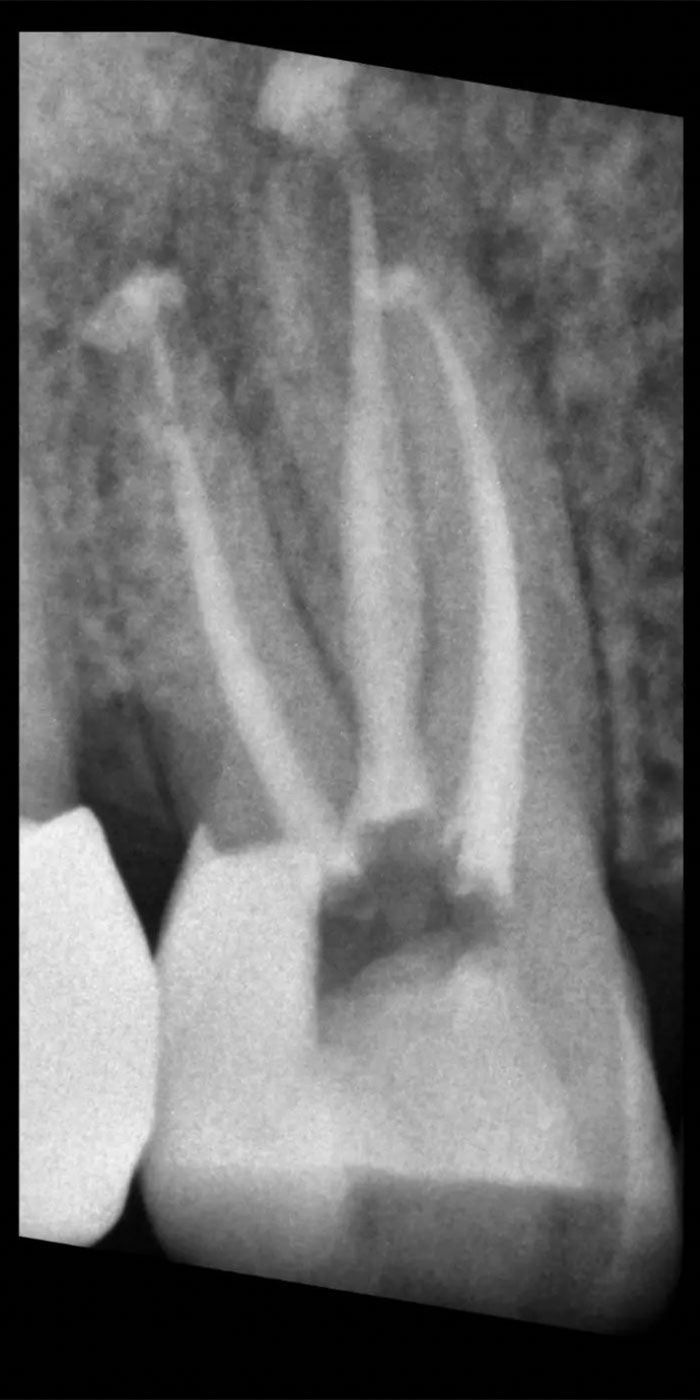

- Our skilled Schenectady root canal dentists will perform a thorough examination and X-rays to assess the extent of damage or infection within the tooth.

- An access point is created in the tooth, and the infected or inflamed pulp is carefully removed to clean and disinfect the root canals.

- The cleaned canals are then filled with a biocompatible material known as gutta-percha, sealing them to prevent further infection.